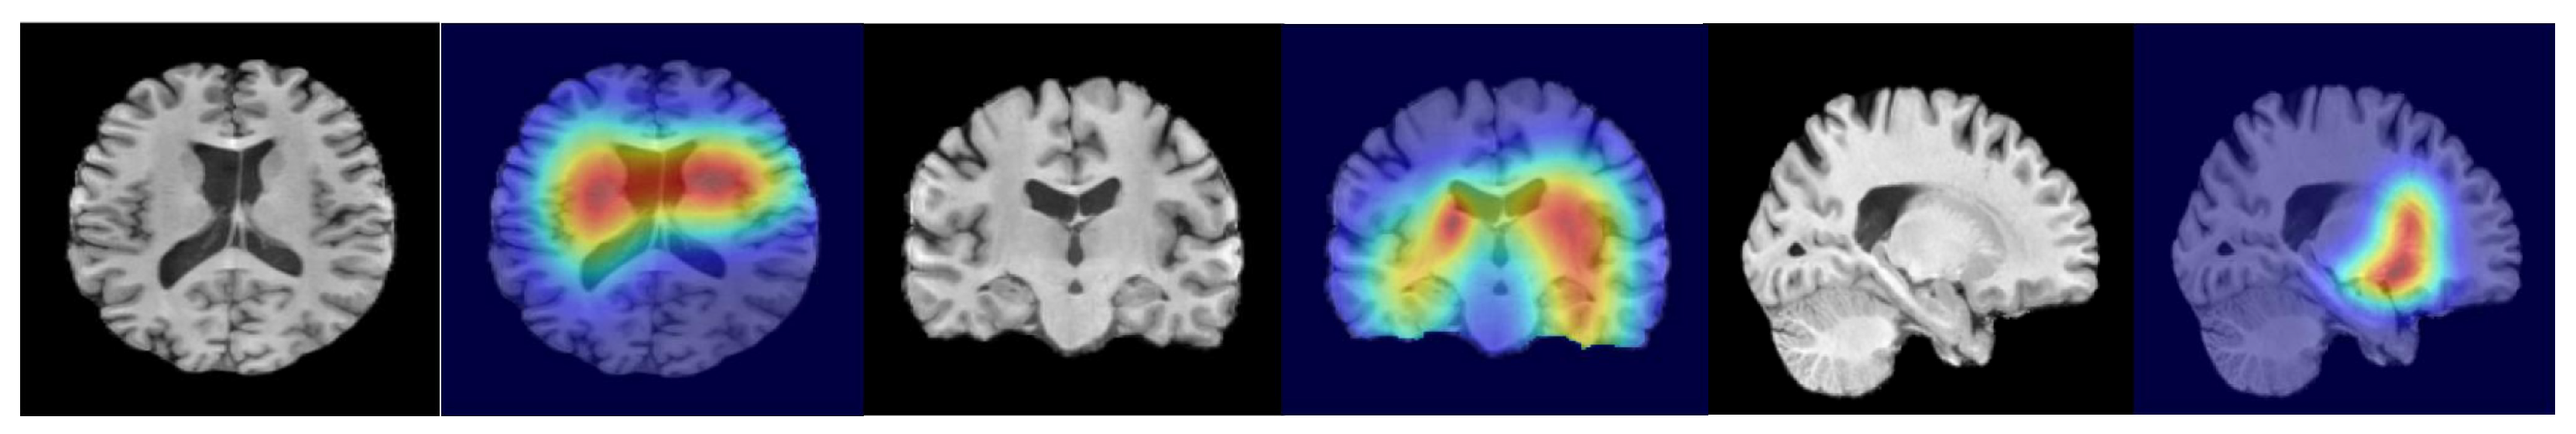

4.2.2. Imaging Analysis